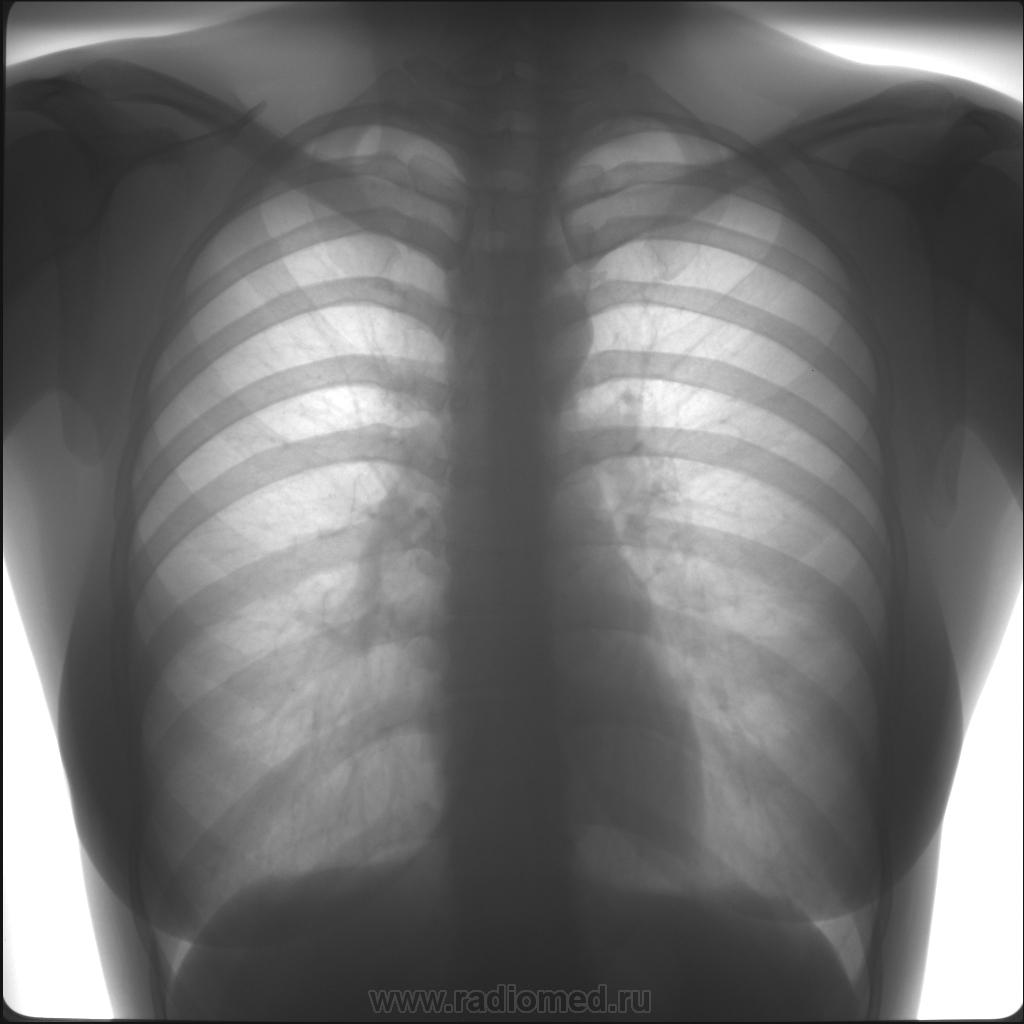

Снимок грудной клетки здорового ребенка: примеры и диагностика

Раздел: Мудрость в объективе